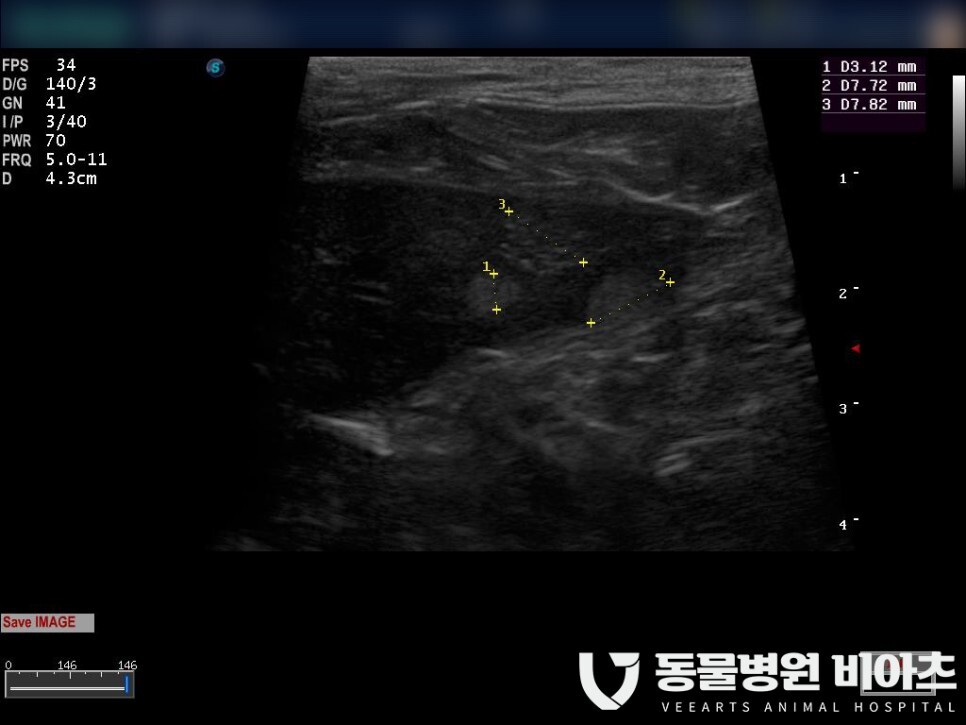

하얀색으로 표시한 부분이 종양입니다.

크기는 약 3cm 정도였습니다.